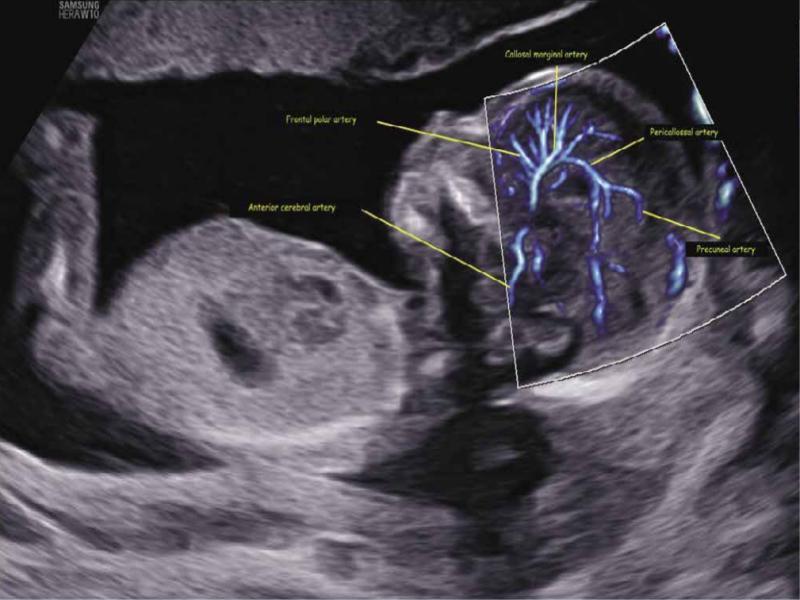

Fig. 1.

Sagittal view of the fetal brain at 16 weeks of gestation showing detailed midline vascular neuroanatomy using both MV-Flow and LumiFlow: frontal polar artery, anterior cerebral artery, callosal marginal artery, pericallosal artery, and pre-cuneal artery